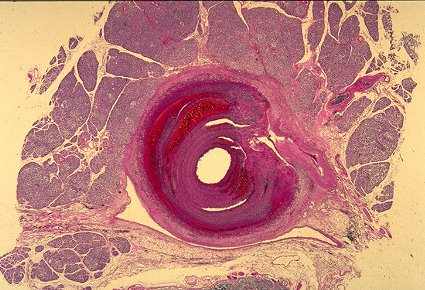

| Small coronary artery with segmental necrosis and inflammation in a patient with Kawasaki disease. |

![]() |

Kawasaki's disease

In the 1960s, the final major category of necrotizing vasculitis was separated from the polyarteritis nodosa group, and this is Kawasaki's disease. Up until this point, there were other descriptions of this process sometimes referred to as infantile form of polyarteritis nodosa because Kawasaki's disease occurs most frequently in young children. However, Kawasaki's disease has another very distinctive component, and this is the mucocutaneous lymph node syndrome. So basically the diagnostic characteristic that separates Kawasaki's disease from polyarteritis nodosa is this mucocutaneous lymph node syndrome with erythematous and scaly mucosa and skin, especially on the digits, with a lymphadenopathy and with this necrotizing vasculitis that has a predilection for the coronary arteries and can produce aneurysms with thrombosis and myocardial infarction. The necrotizing lesion is similar to that of polyarteritis nodosa, although there are some subtle differences in general -- a little less fibrinoid necrosis, a little more cellular character to the initial injury.